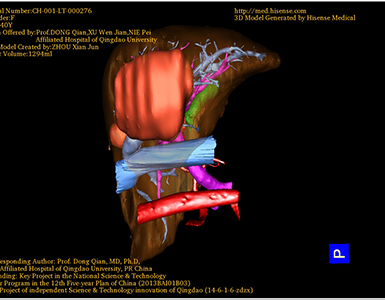

将0.625mm双源薄层CT资料的静脉期和动脉期Dicom格式文件导入海信CAS系统。

通过调节窗宽窗位调整CT序号,对肿瘤,肝实质,胆囊,下腔静脉,肿瘤,肝动脉、门静脉及肝静脉等进行三维重建;系统自动计算肿瘤体积和肝脏体积。

模拟手术操作,自动计算切除肿瘤体积。肝脏体积为1294ml,肿瘤体积为158.5ml,肿瘤体积为肝脏体积的12.2%,通过比对40-50岁正常肝脏体积为1368.38±279.24 ml,通过术前模拟手术,精准判断切除后剩余肝脏体积能耐受,避免肝衰竭发生。

术前三维重建:重建图片

重建视频